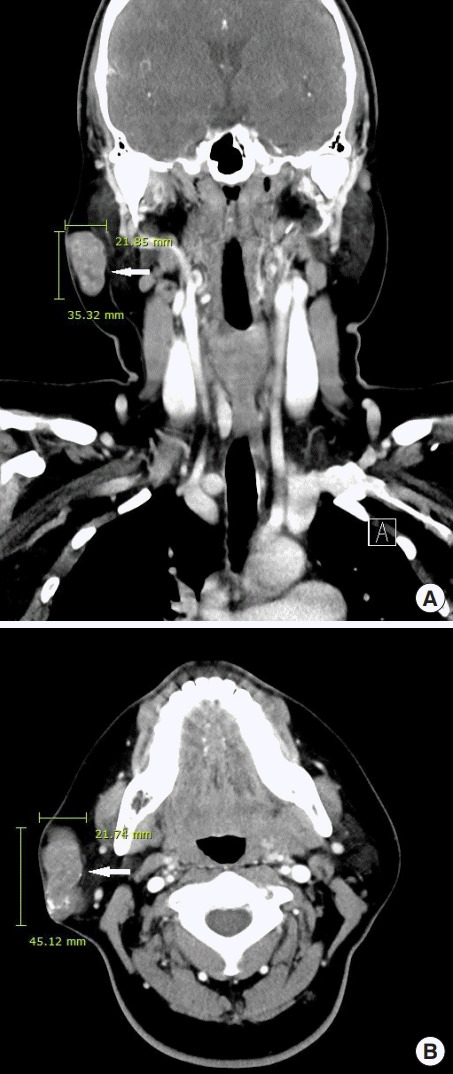

進(jìn)行超聲檢查以確定腫塊是否為腮腺腫瘤,并顯示與腮腺分離的異質(zhì)腫塊(圖 2)。 進(jìn)行了頸部對比增強(qiáng)計算機(jī)斷層掃描和超聲引導(dǎo)穿刺活檢。 在右下頜角,它表現(xiàn)為邊界清楚、分葉狀和不均勻強(qiáng)化的腫瘤,在皮下脂肪層和淺表肌肉腱膜系統(tǒng)中有鈣化部分(圖 3)。 穿孔活檢顯示與毛母質(zhì)瘤一致的特征,并且在超聲引導(dǎo)下對頸部淋巴結(jié)進(jìn)行抽吸活檢時未發(fā)現(xiàn)腫瘤細(xì)胞。

圖 3:頸部對比增強(qiáng)計算機(jī)斷層掃描的冠狀 (A) 和軸位 (B) 視圖顯示右腮腺區(qū)域(箭頭)中邊界清楚、分葉狀、不均勻的病變。